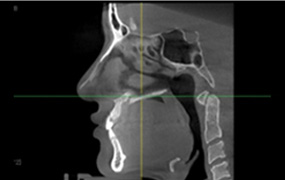

3D-CT

입체분석

을 통한

심층검사

수술 전 3D-CT 입체 분석을 통해

환자의 코 뼈는 물론 코 주변 연부 조직의

모양, 상태, 크기까지 정밀하게 검사하여

환자 개개인에 맞는 1:1 맞춤 수술을 계획합니다.

연골 비대칭 및

비중격 만곡증의 유무

하비갑개 비후 및

코막힘 문제해결

비중격 연골의

상태와 크기 분석

코 뼈의 넓이